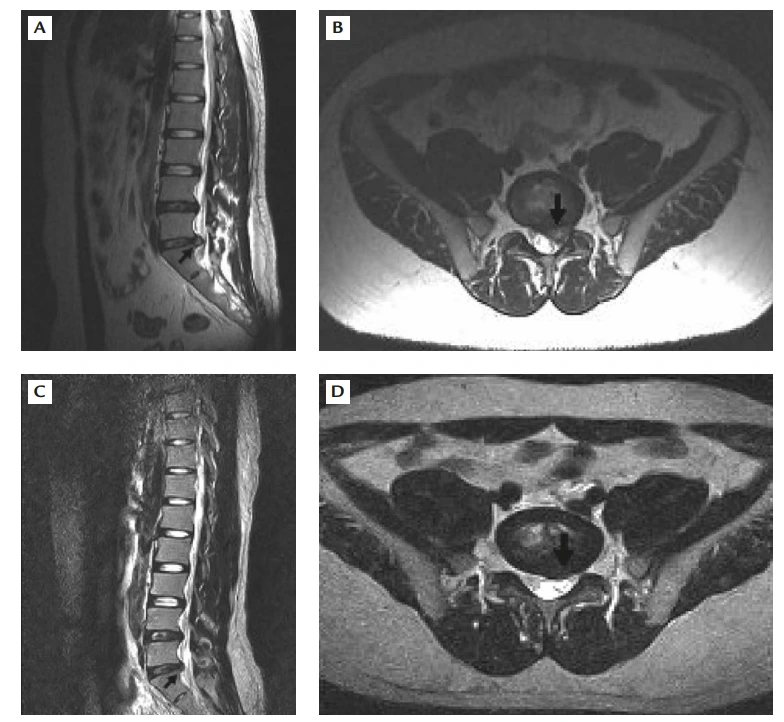

실제 환자 사례를 보자.

A&B 사진에 표시되어 있는 부분을 보면, 요추 4번 - 요추 5번 사이에 디스크가 왼쪽으로 돌출되어 나왔다. 환자 분은 허리 통증 및 좌측 다리 방사통을 심하게 호소했다. 하지만 마비 등의 증상은 없어 보존적 치료(약물치료, 휴식)를 시행했다.

C&D 사진은 30개월 이후의 mri 사진이다. 이전에 보이던 디스크 돌출은 거의 흡수되어 없어졌다. 환자 역시 증상은 호전되었다.

Chang et al. Spontaneous regression of lumbar herniated disc. J Chin Med Assoc. 2009